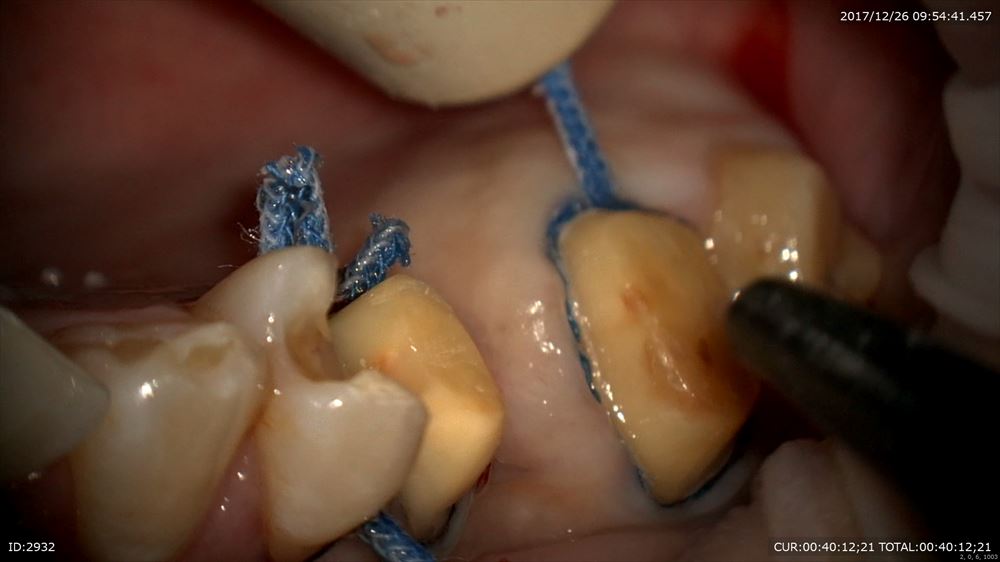

まず型取りの準備

シリコンを使用し採れた型を観察しチエック

倍率をあげて(8倍)チェック歯茎の内部まで流れているか。。

いいね。マイクロスコープがなければ観察できないです。